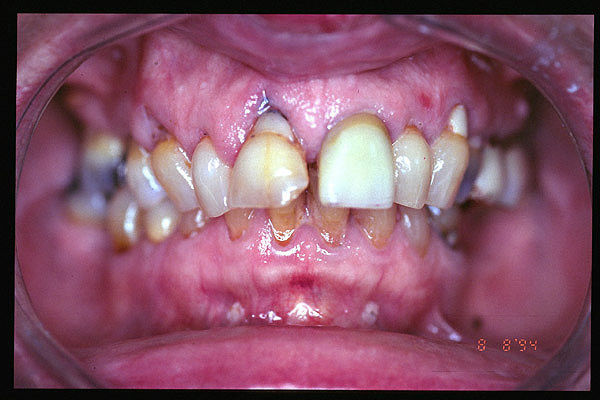

CM Enfermedad periodontal avanzada con caries. Mala higiene.